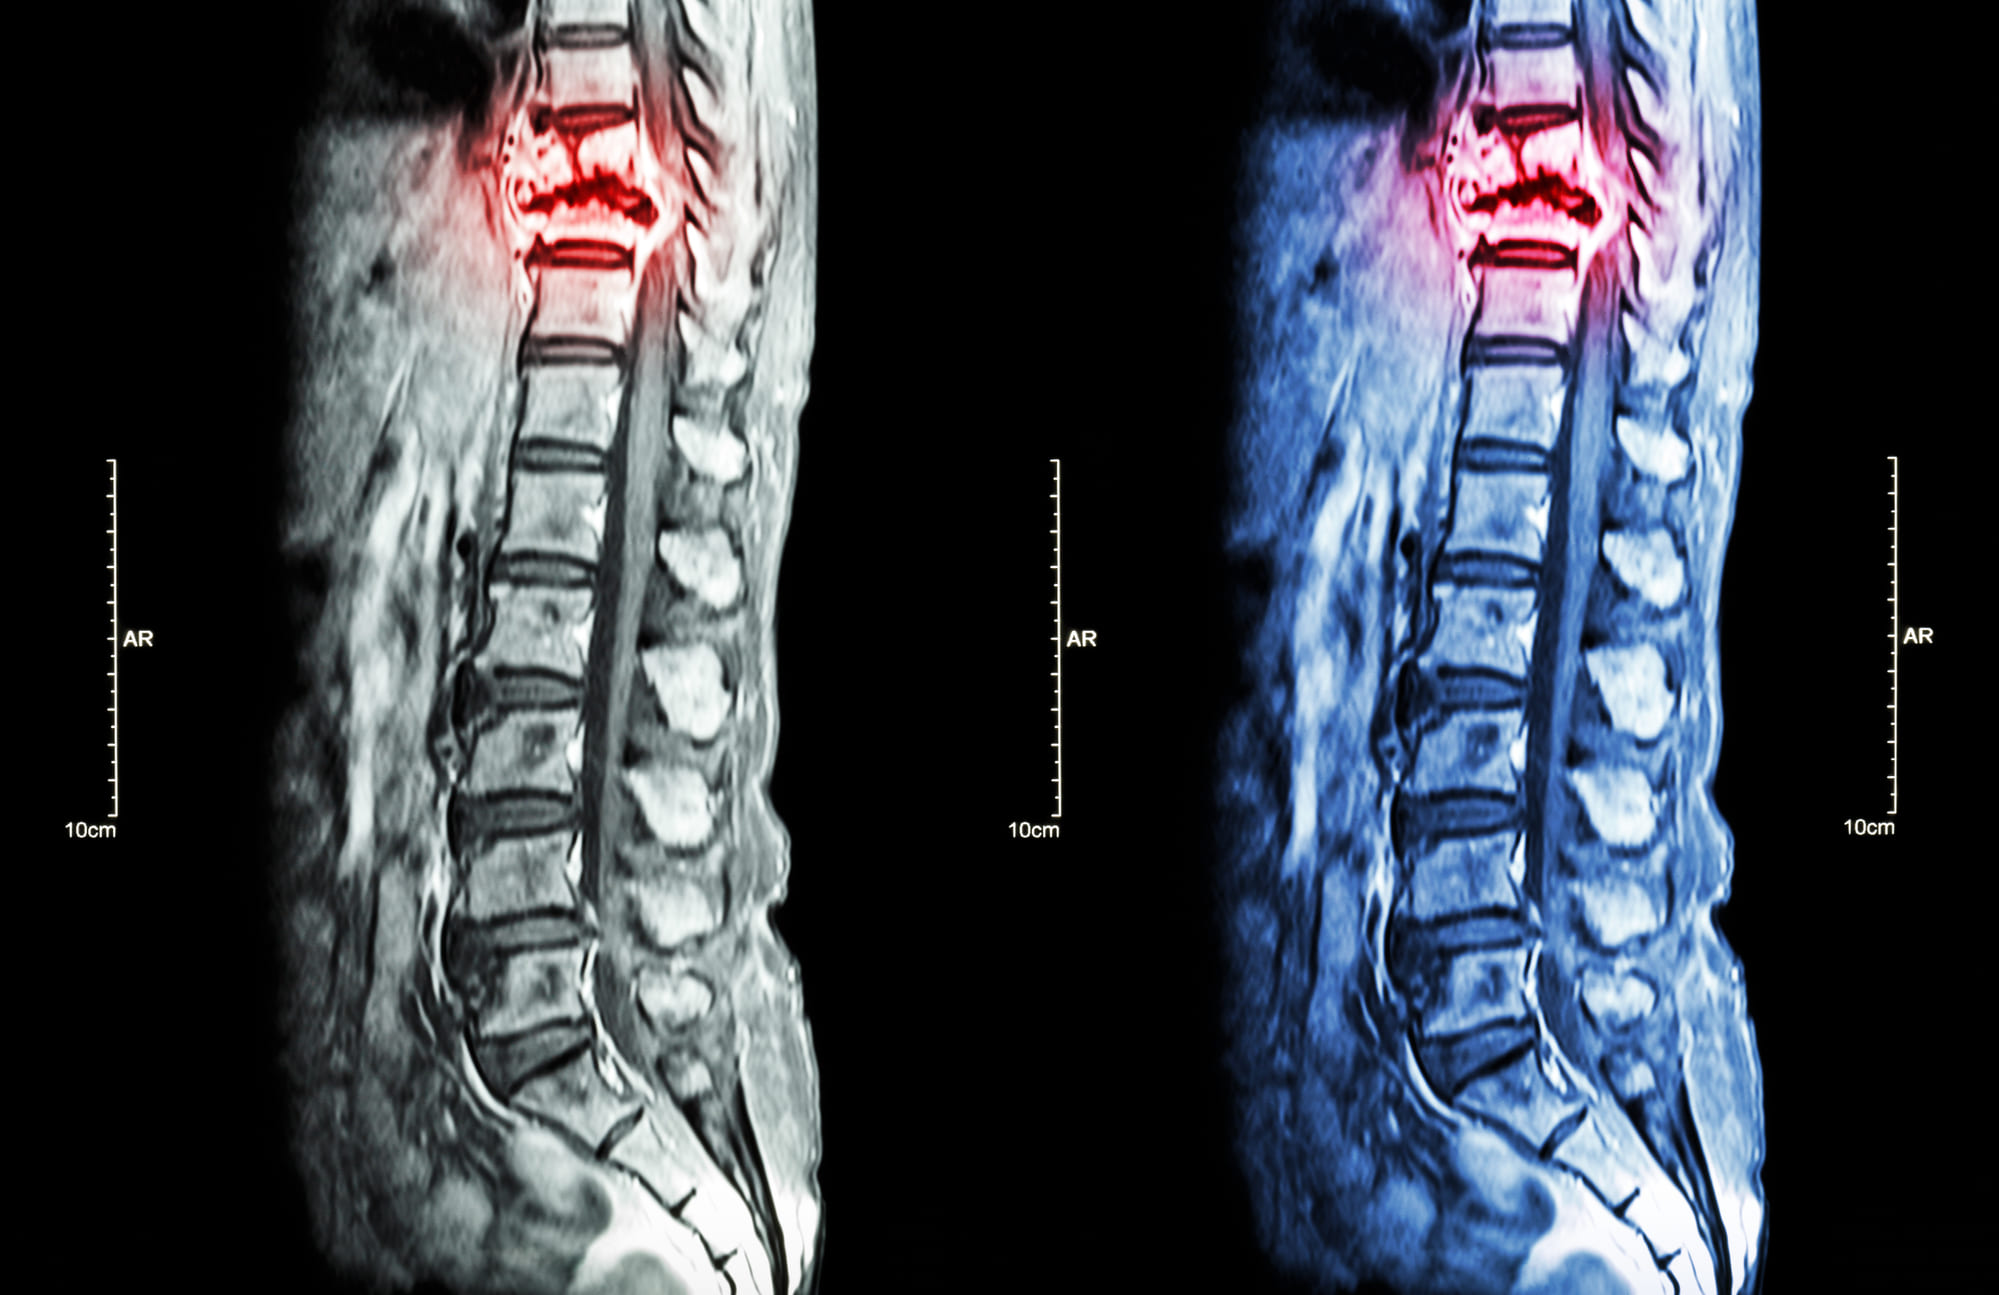

Spinal operations are always a delicate procedure that requires preparation in advance and that a doctor and a physiotherapist should always supervise the postoperative procedure to verify that it is all well and that the patient can reacquire his motor skills, as well as he or she, can without problems. As it is the major axis supporting the motor system, knowing how to recover after spinal surgery is highly essential.

Advanced NeuroSpinal Care experts bring a data-based, interdisciplinary method to handle spine complications. We monitor you and try to recognize the actual reason of your discomfort or other signs.

The spine is the core of our health. It uniquely affects a human being’s complete quality of life. Trust us in our purpose to guide you to the appropriate expert immediately to evade unneeded meetings at the clinic.